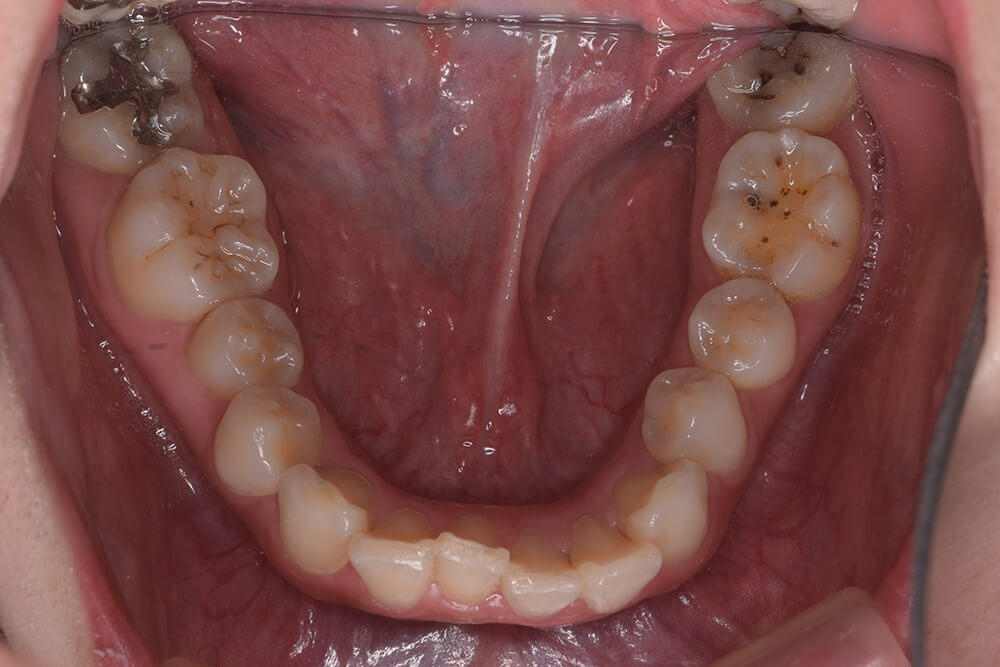

CASE03

Before